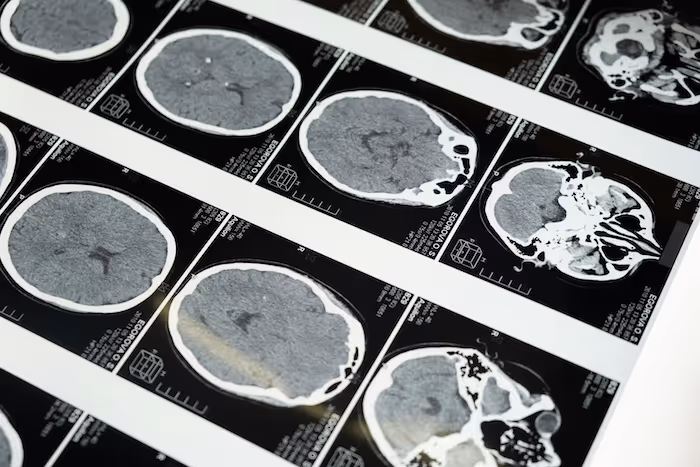

MRI datasets require precise and structured annotation to support AI systems that analyze soft tissue, neurological structures, musculoskeletal regions, and pathology related patterns. MRI presents unique challenges such as variable contrast, anatomical complexity, and multi sequence variation.

MRI annotation labels magnetic resonance imaging data so that AI models can learn to segment anatomical structures, detect and characterize pathological findings, and support clinical decision-making from MRI. It includes volumetric organ segmentation (brain, liver, kidney, prostate, heart, spinal cord), lesion detection and characterization (tumor location, size, boundaries, signal characteristics), tissue classification (white matter, gray matter, cerebrospinal fluid in neuroimaging), and functional MRI annotation for neuroscience applications. MRI annotation requires radiologists or subspecialty physicians with MRI interpretation training because the relevant findings require clinical expertise to identify correctly from MRI contrast characteristics.

MRI annotation faces several challenges that make it more demanding than standard image annotation. MRI produces 3D volumetric data rather than 2D images: each scan consists of dozens to hundreds of axial slices that must be annotated consistently as a 3D structure, requiring annotators to trace boundaries across all slices. Different MRI sequences (T1, T2, FLAIR, DWI, DCE) show tissue differently and each requires sequence-specific interpretation knowledge. Signal intensity does not have absolute calibration (unlike CT Hounsfield units), making intensity-based classification dependent on relative contrast rather than absolute thresholds. These characteristics require radiologist expertise and specialized annotation tools that support multi-planar viewing and 3D brush annotation.

What is brain MRI annotation and why is it particularly complex?

Brain MRI annotation is one of the most complex annotation categories in medical AI because the brain contains hundreds of anatomical structures with complex 3D morphology, and pathological findings span a wide range of conditions (tumors, stroke, demyelination, atrophy, vascular disease) that each require subspecialty knowledge to characterize accurately. Standard neuroimaging annotation tasks include white matter lesion segmentation (for multiple sclerosis monitoring), glioma segmentation and grading (BraTS challenge tasks), hippocampal segmentation for Alzheimer's disease research, and anatomical parcellation for neuroscience research. Each task requires neuroimaging-specialized radiologists or neuroscientists as annotators.